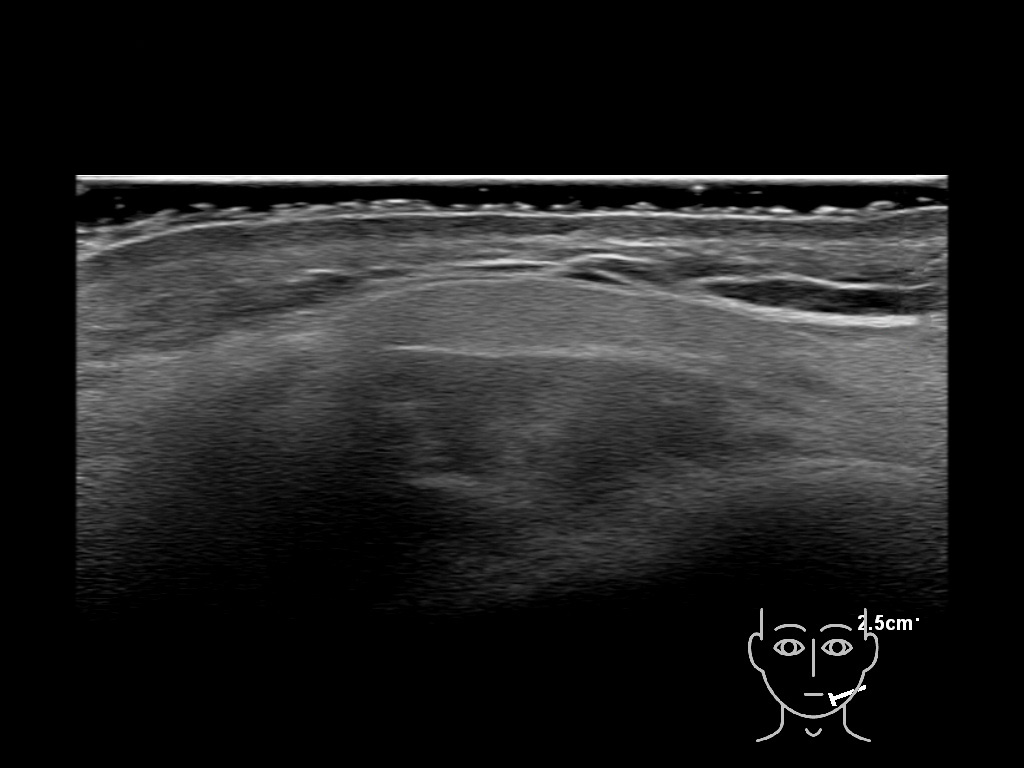

Filler deposits may end up unintentionally in the SMAS or fascial layers of the skin. Very often this will not lead to adverse events, however, adverse events ( nodules, migration / redistribution impaired muscle movement and smiling and malar edema) are are often related to filler ending up in the SMAS or fascia.

Study the first image to recognize the different layers. If you are sure about the layers, swipe to the second image to view the answer (if applicable).